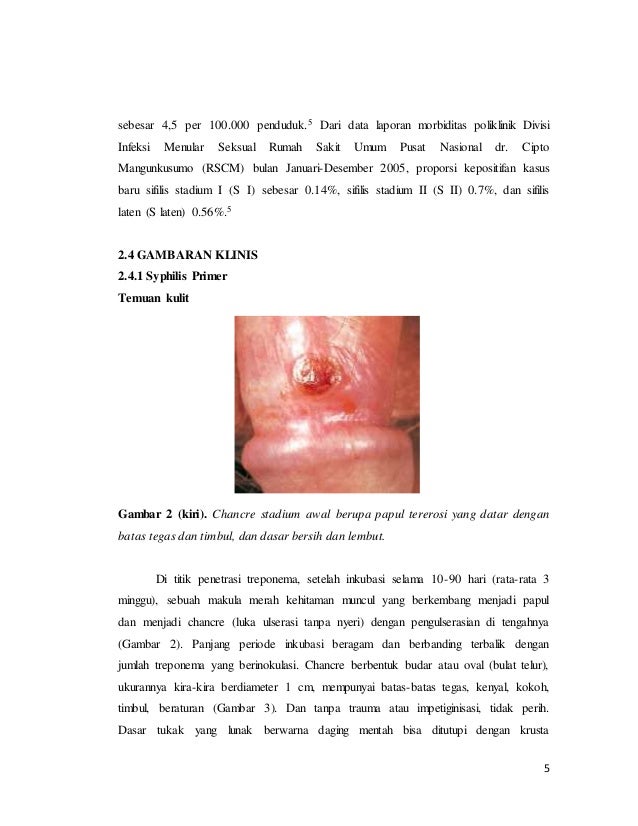

5 BAB II TINJAUAN PUSTAKA A. Sifilis Sifilis adalah penyakit menular seksual yang ditandai dengan adanya lesi primer kemudian di

BAB 2 TINJAUAN PUSTAKA 2.1. Penyakit Sifilis Sifilis adalah

BAB 2 TINJAUAN PUSTAKA 2.1. Penyakit Sifilis Sifilis adalah